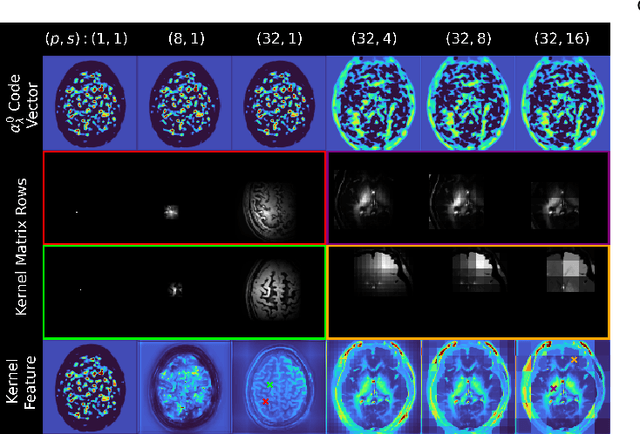

Abstract:Low-dose positron emission tomography (PET) image reconstruction methods have potential to significantly improve PET as an imaging modality. Deep learning provides a promising means of incorporating prior information into the image reconstruction problem to produce quantitatively accurate images from compromised signal. Deep learning-based methods for low-dose PET are generally poorly conditioned and perform unreliably on images with features not present in the training distribution. We present a method which explicitly models deep latent space features using a robust kernel representation, providing robust performance on previously unseen dose reduction factors. Additional constraints on the information content of deep latent features allow for tuning in-distribution accuracy and generalisability. Tests with out-of-distribution dose reduction factors ranging from $\times 10$ to $\times 1000$ and with both paired and unpaired MR, demonstrate significantly improved performance relative to conventional deep-learning methods trained using the same data. Code:https://github.com/cameronPain